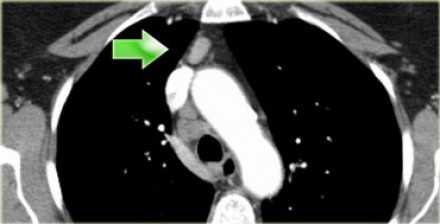

Лимфатические узлы 3 группы не примыкают к трахее в отличии от лимфатических узлов 2 группы. Они подразделюятся на: 3А кпереди от сосудов 3Р позади пищевода/превертебрально Они не доступны при медиастиноскопии. 3Р группа может быть доступна при чреспищеводной эхокардиографии.

На изображении слева 3А узел в преваскулярном пространстве. Обратите внимание так же на ниже расположенные паратрахеальные узлы справа относящиеся к 4R группе.